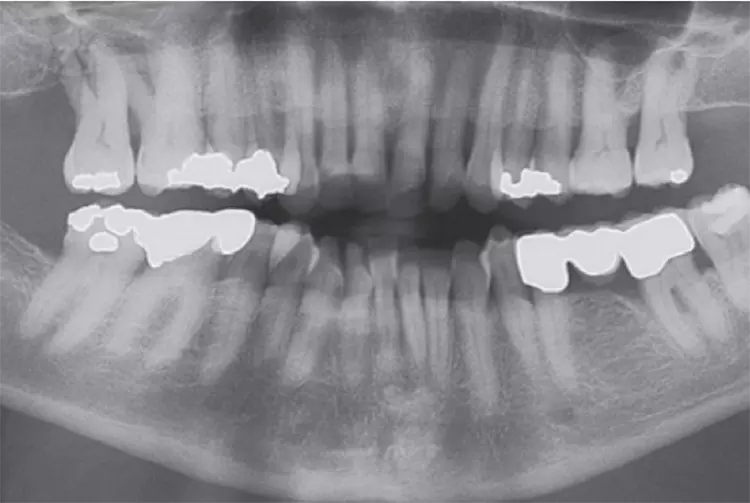

Sofortimplantationen regiones 33, 31, 41 und 43 mit vier PATENTs (Zircon-Medical AG, im Vertrieb der Champions-Implants GmbH). Nach drei Monaten post OP wurden die Glasfaser-Post Aufbauten in die C-Connection der PATENTS mit Relyx Unicem supragingival eingeklebt und für eine Zirkon-Steg-Aufnahme präpariert. Das Sekundär-Gerüst wurde aus PEEK erstellt und die gut balancierte Prothese eingegliedert (Abb. 38-46).